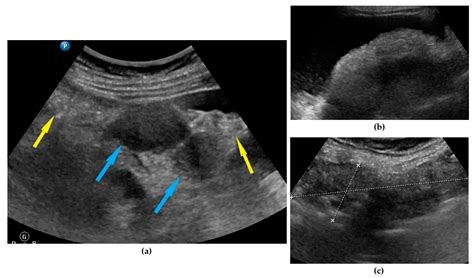

When a radiologist or sonographer performs an ovarian cancer ultrasound, they are looking for specific morphological patterns. A normal ovary usually has a smooth, consistent texture. When potential malignancy is suspected, the following "red flags" may be noted:

• Solid Components: Fluid-filled cysts are often benign, but solid masses within an ovarian cyst can be more concerning.

• Irregular Borders: A mass with thick, irregular walls or "papillary projections" (small, finger-like growths inside or outside the cyst) is generally viewed with higher suspicion.

• Ascites: The presence of free fluid in the abdomen can sometimes be associated with more advanced ovarian cancer.